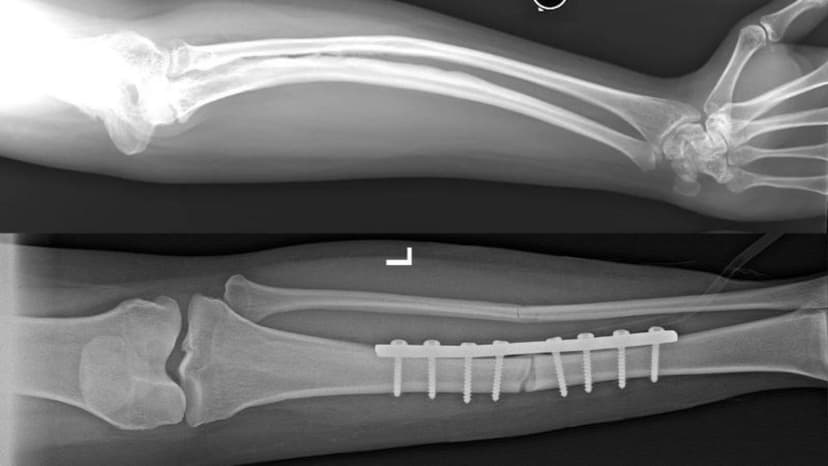

- Vấn đề về xương và hệ vận động:

- Xương sườn mỏng, xương chậu kém phát triển, cột sống có thể bị nứt.